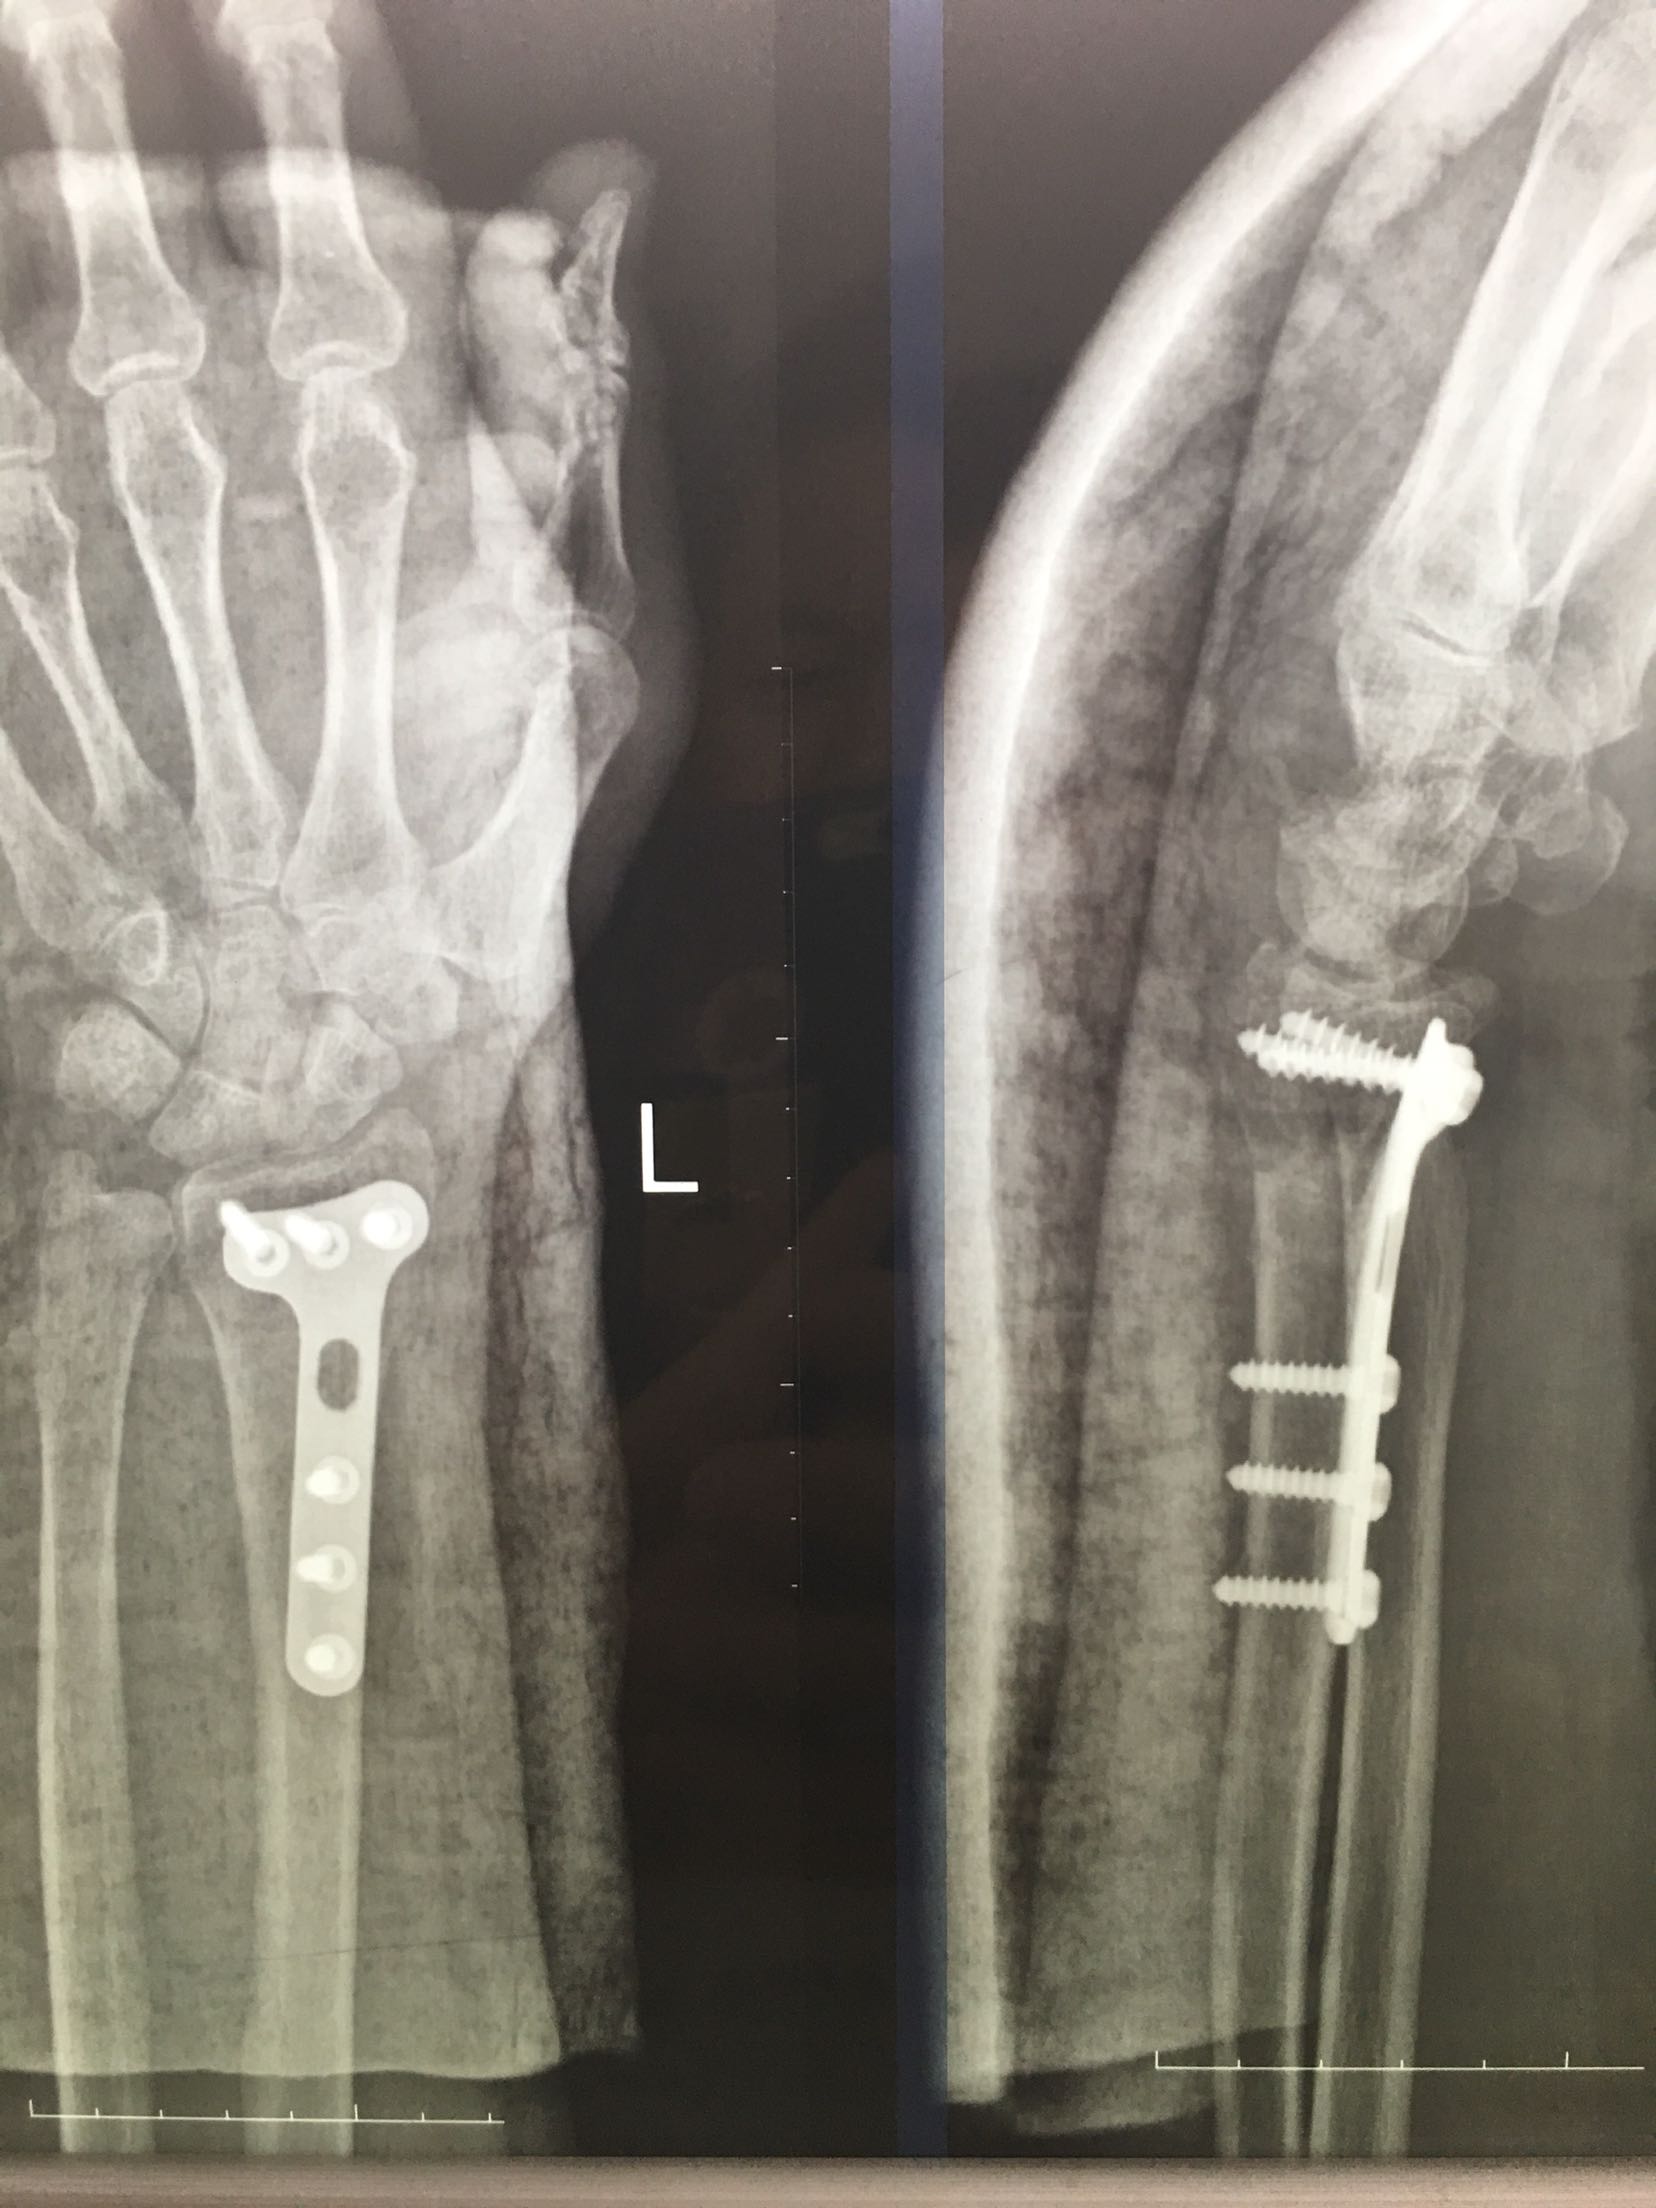

尺桡骨远端骨折

桡骨远端骨折尺骨茎骨折和下桡尺关节分离

右尺桡骨骨折

桡骨远端骨折